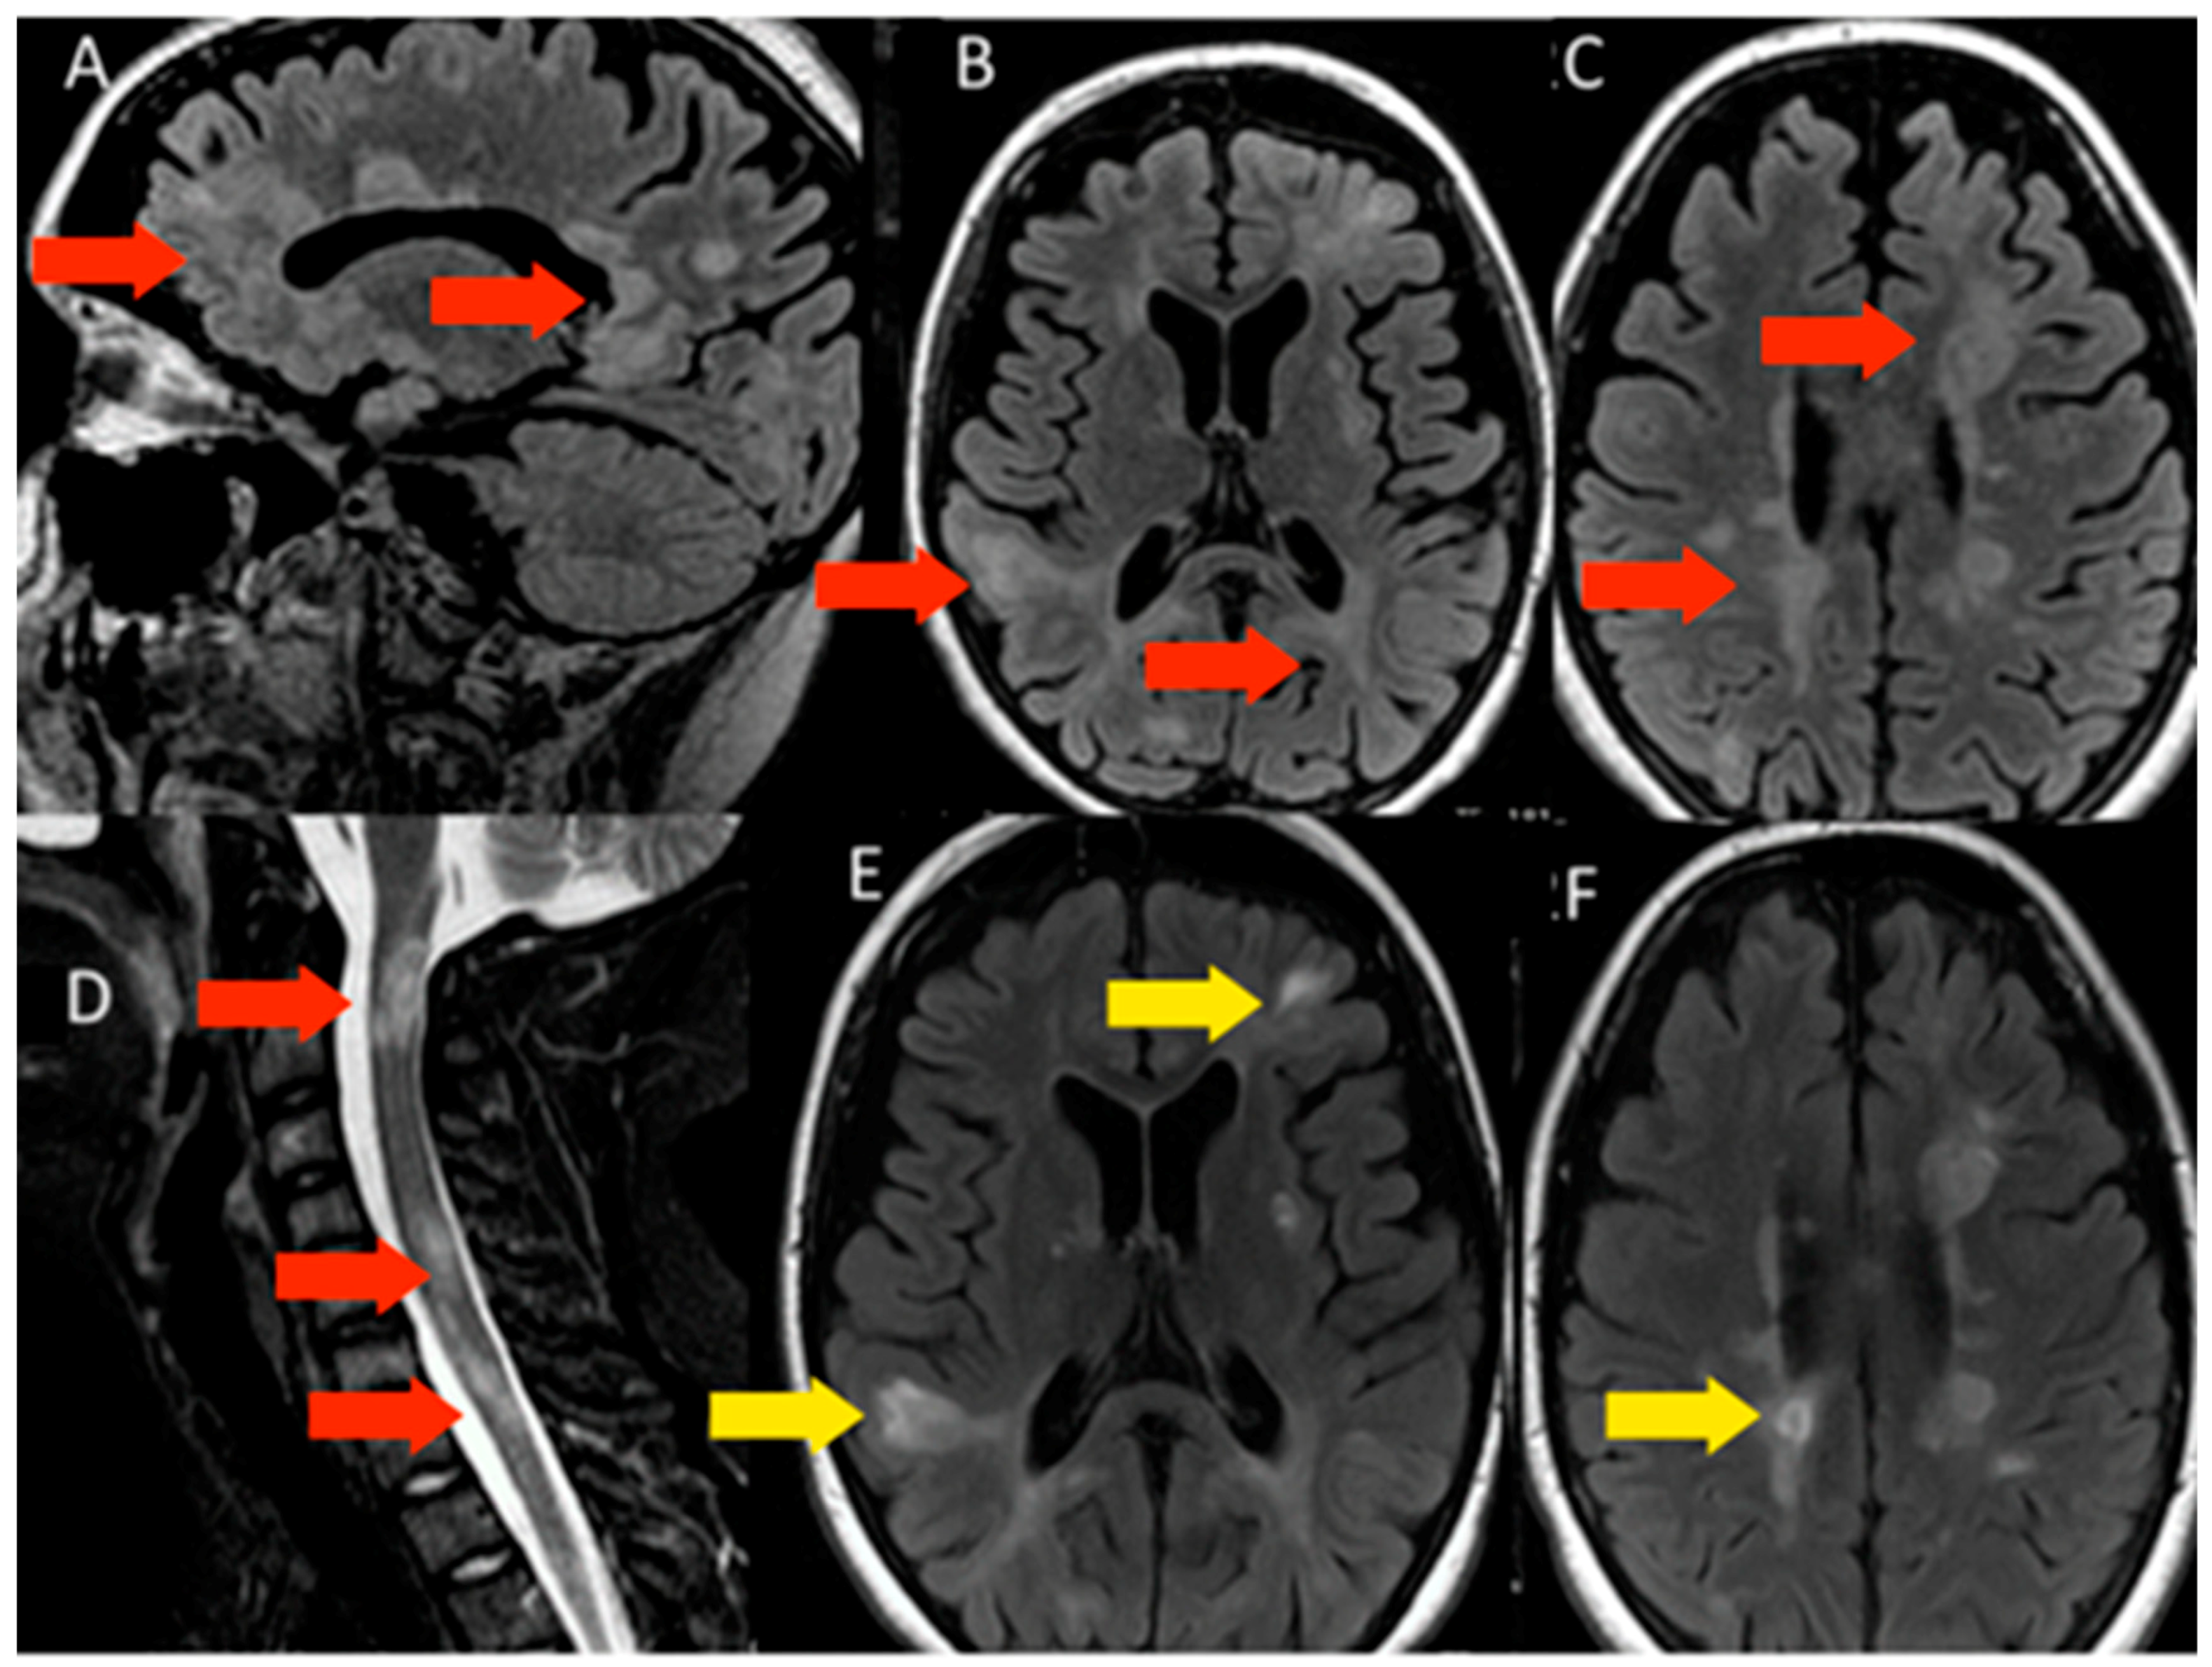

3.1.2. Patient 2